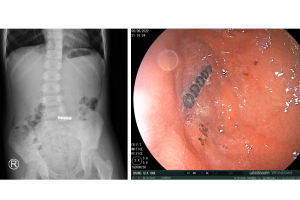

Tuần qua, Bệnh viện Nhi Đồng Thành Phố tiếp nhận một trường hợp trẻ Tr. D. A. 7 tuổi, nam, cân nặng 38 kg, ngụ ở Vĩnh Lộc B, Bình Chánh. Khai thác bệnh sử ghi...